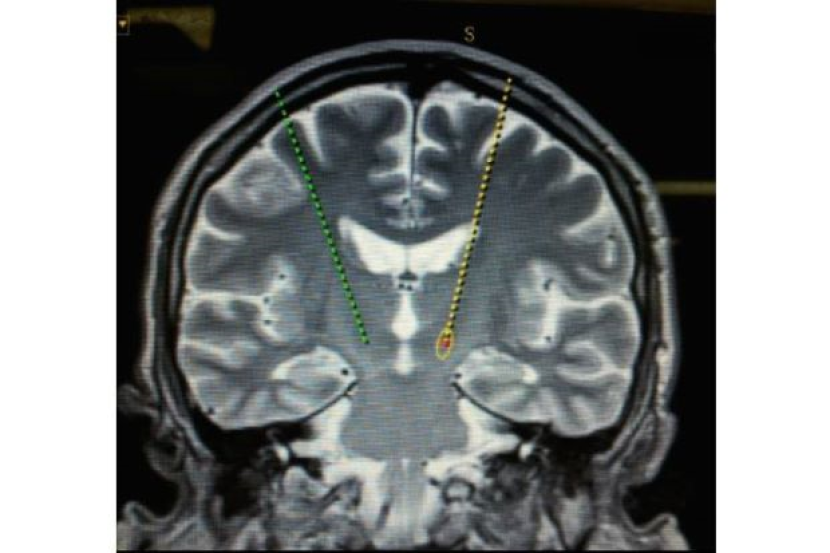

Menjelaskan dengan lebih lanjut mengenai prosedur itu, Dr Jegan berkata, pasukan pembedahan memasukan dua elektrod berukuran diameter 1.27mm setiap satu ke dalam kawasan sasaran di dalam otak pesakit warga emas.

"Elektrod itu disambung kepada perentak jantung yang diimplan di bahagian dada."Pesakit dalam keadaan sedar sepanjang prosedur supaya ujian dapat dilakukan dengan serta-merta dan keputusan dapat dilihat didalam bilik pembedahan," katanya.